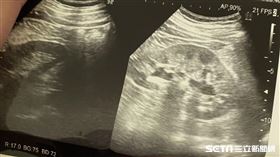

可怕!腎臟長癌了 大肚男:沒啥不適

定期健康檢查之所以重要,一大原因在於癌症等重大疾病在...

養身婦無痛血尿2周 檢查已經第3期

新竹57歲劉姓婦人平時吃的都很養身,但2週以來陸續出...

腎結石意外讓大魔王現形 他直呼感謝

腎結石發作痛起來要人命,這可能是每一位病患的心聲。臨...